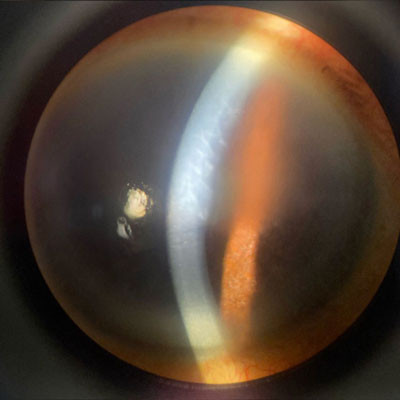

When considering uveitis and cataract surgery, you could be dealing with a patient who you know has uveitis, or you could have a patient who develops a new uveitis after surgery. Three physicians spoke about preop, surgery, and postop considerations.